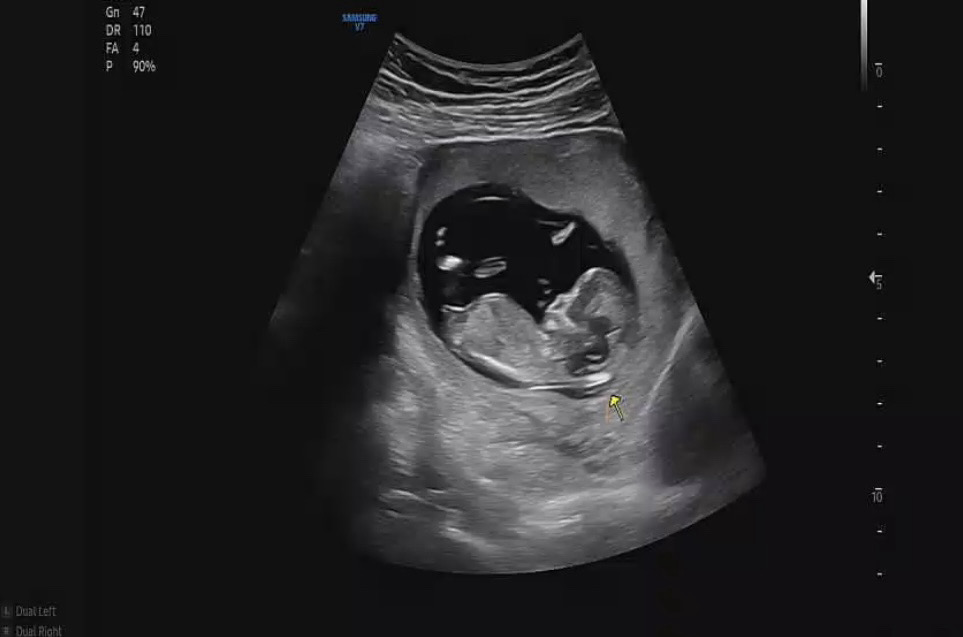

12주 1일차 각도법 좀 봐주세요ㅠㅠ

각도법 좀 봐주세요ㅠㅠ!!